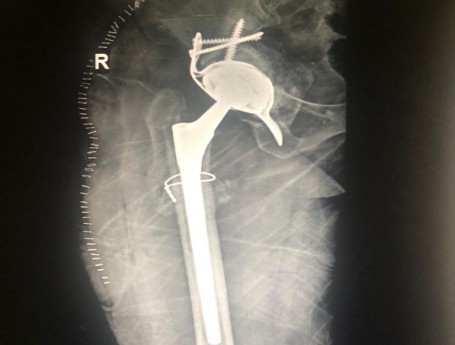

Revision Total Hip Arthroplasty

Revision Total Hip Arthroplasty Femoral Stem